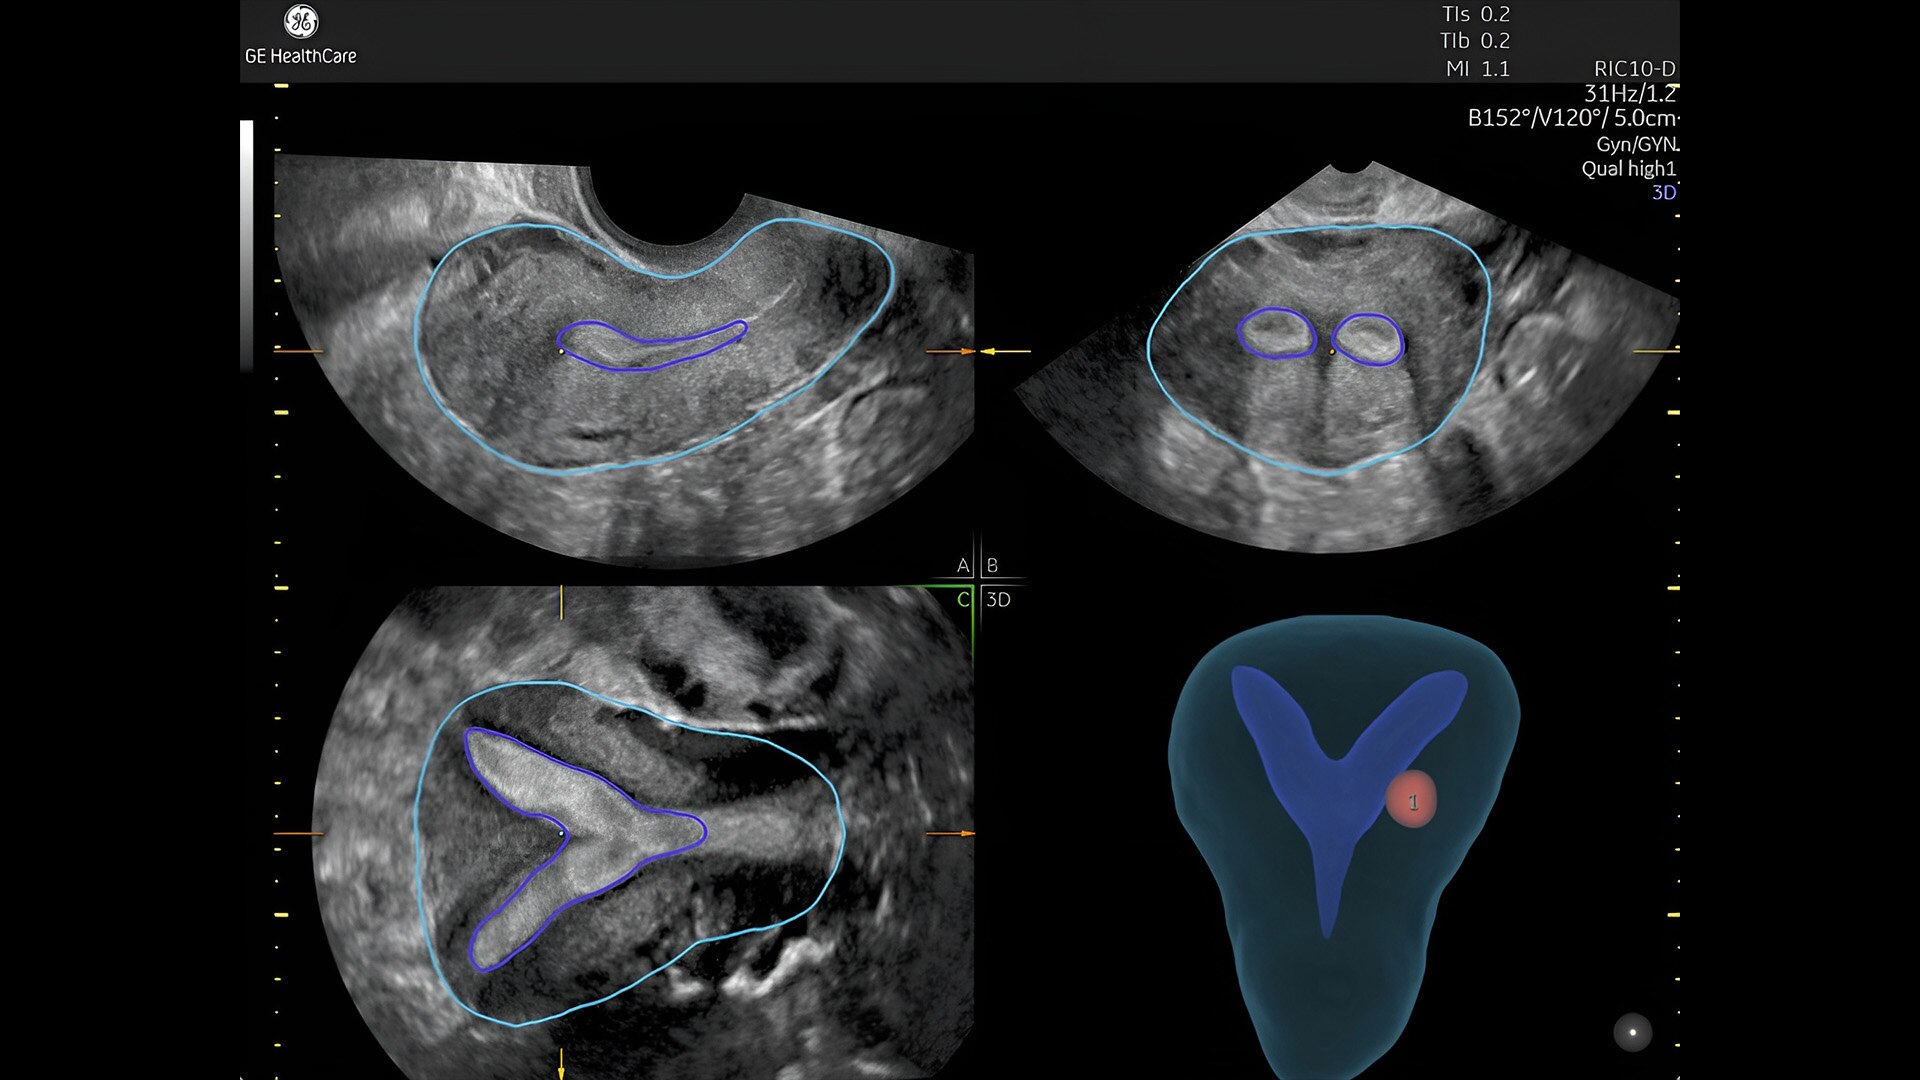

Pelvic health

Offer patient answers faster with Ai-based automation tools

Complex cases come with enough uncertainty. That's why the Voluson Expert 22 is specifically designed for in-depth assessment of complicated anatomy — with pioneering first trimester, fetal cardiac, gynecological, and other pivotal technologies that focus on early detection and intervention.